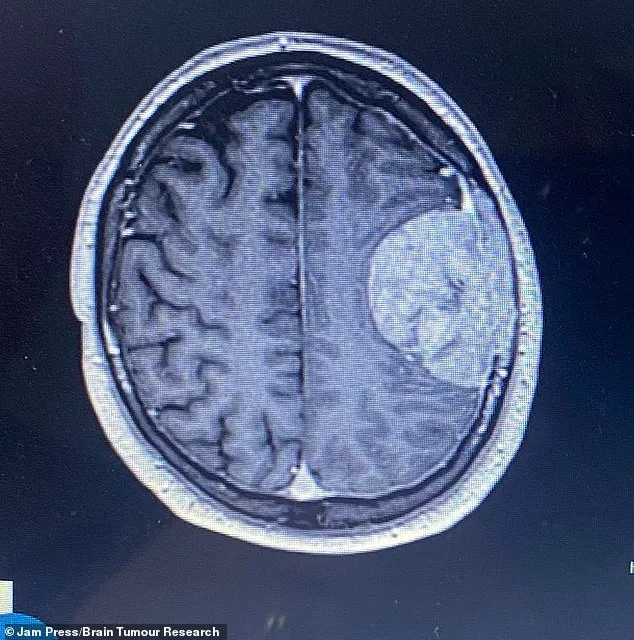

In April 2025, everything changed. One moment, Stuart was in the bathroom; the next, he emerged unable to form a single word or lift his arms. His wife, Bev Hill, immediately feared a stroke and called an ambulance. When the paramedics arrived, they noted a partial return of his speech, but they rushed him to Southmead Hospital in Bristol for urgent scans. By 3am, the results were in: no stroke, but a mass on his brain. The discovery left the family reeling. Was this a new development, or had this tumor been growing undetected for years? The answers would come later, but the initial shock was profound.

Doctors began treating Stuart with steroids to reduce brain swelling while conducting further tests. They found no evidence of cancer elsewhere in his body, which led them to believe the tumor was slow-growing and possibly benign. Yet, the risks of surgery were severe. A stroke, death, or permanent neurological damage were all possible outcomes. Bev Hill recalls the heart-wrenching moment she learned the news: 'It was the worst possible news. My first thought was how we were going to tell our daughters, Megan and Jodie.' The weight of uncertainty hung over the family like a storm cloud.

Initial scans suggested Stuart's speech difficulties were due to post-surgical swelling. However, a later MRI revealed something more alarming: a stroke had occurred. The stroke had affected the brain's language centers, leaving Stuart with lasting speech impairments. Nearly 10 months after the operation, he is still struggling to communicate. He also experienced a seizure, now requiring anti-seizure medication twice daily. The family's ordeal was far from over.